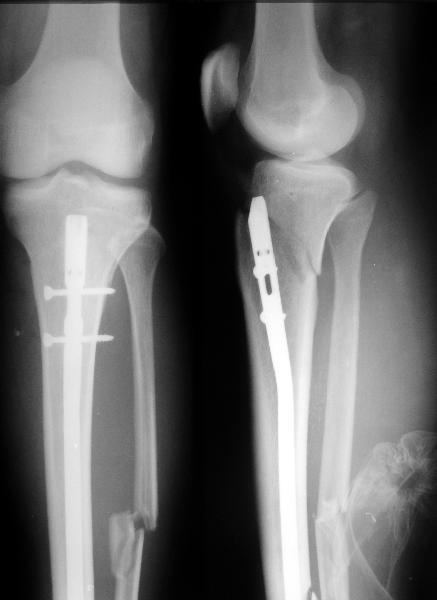

I applied a simple Ilizarov frame, and after reduction inserted a locking screw into a 45 degree hole and two AP screws "miss a nail".

X-rays attached.

Так и сделали. Плюс винт в 45 градусное отверстие и два в передне-заднем направлении. Снимок в приложении выше.